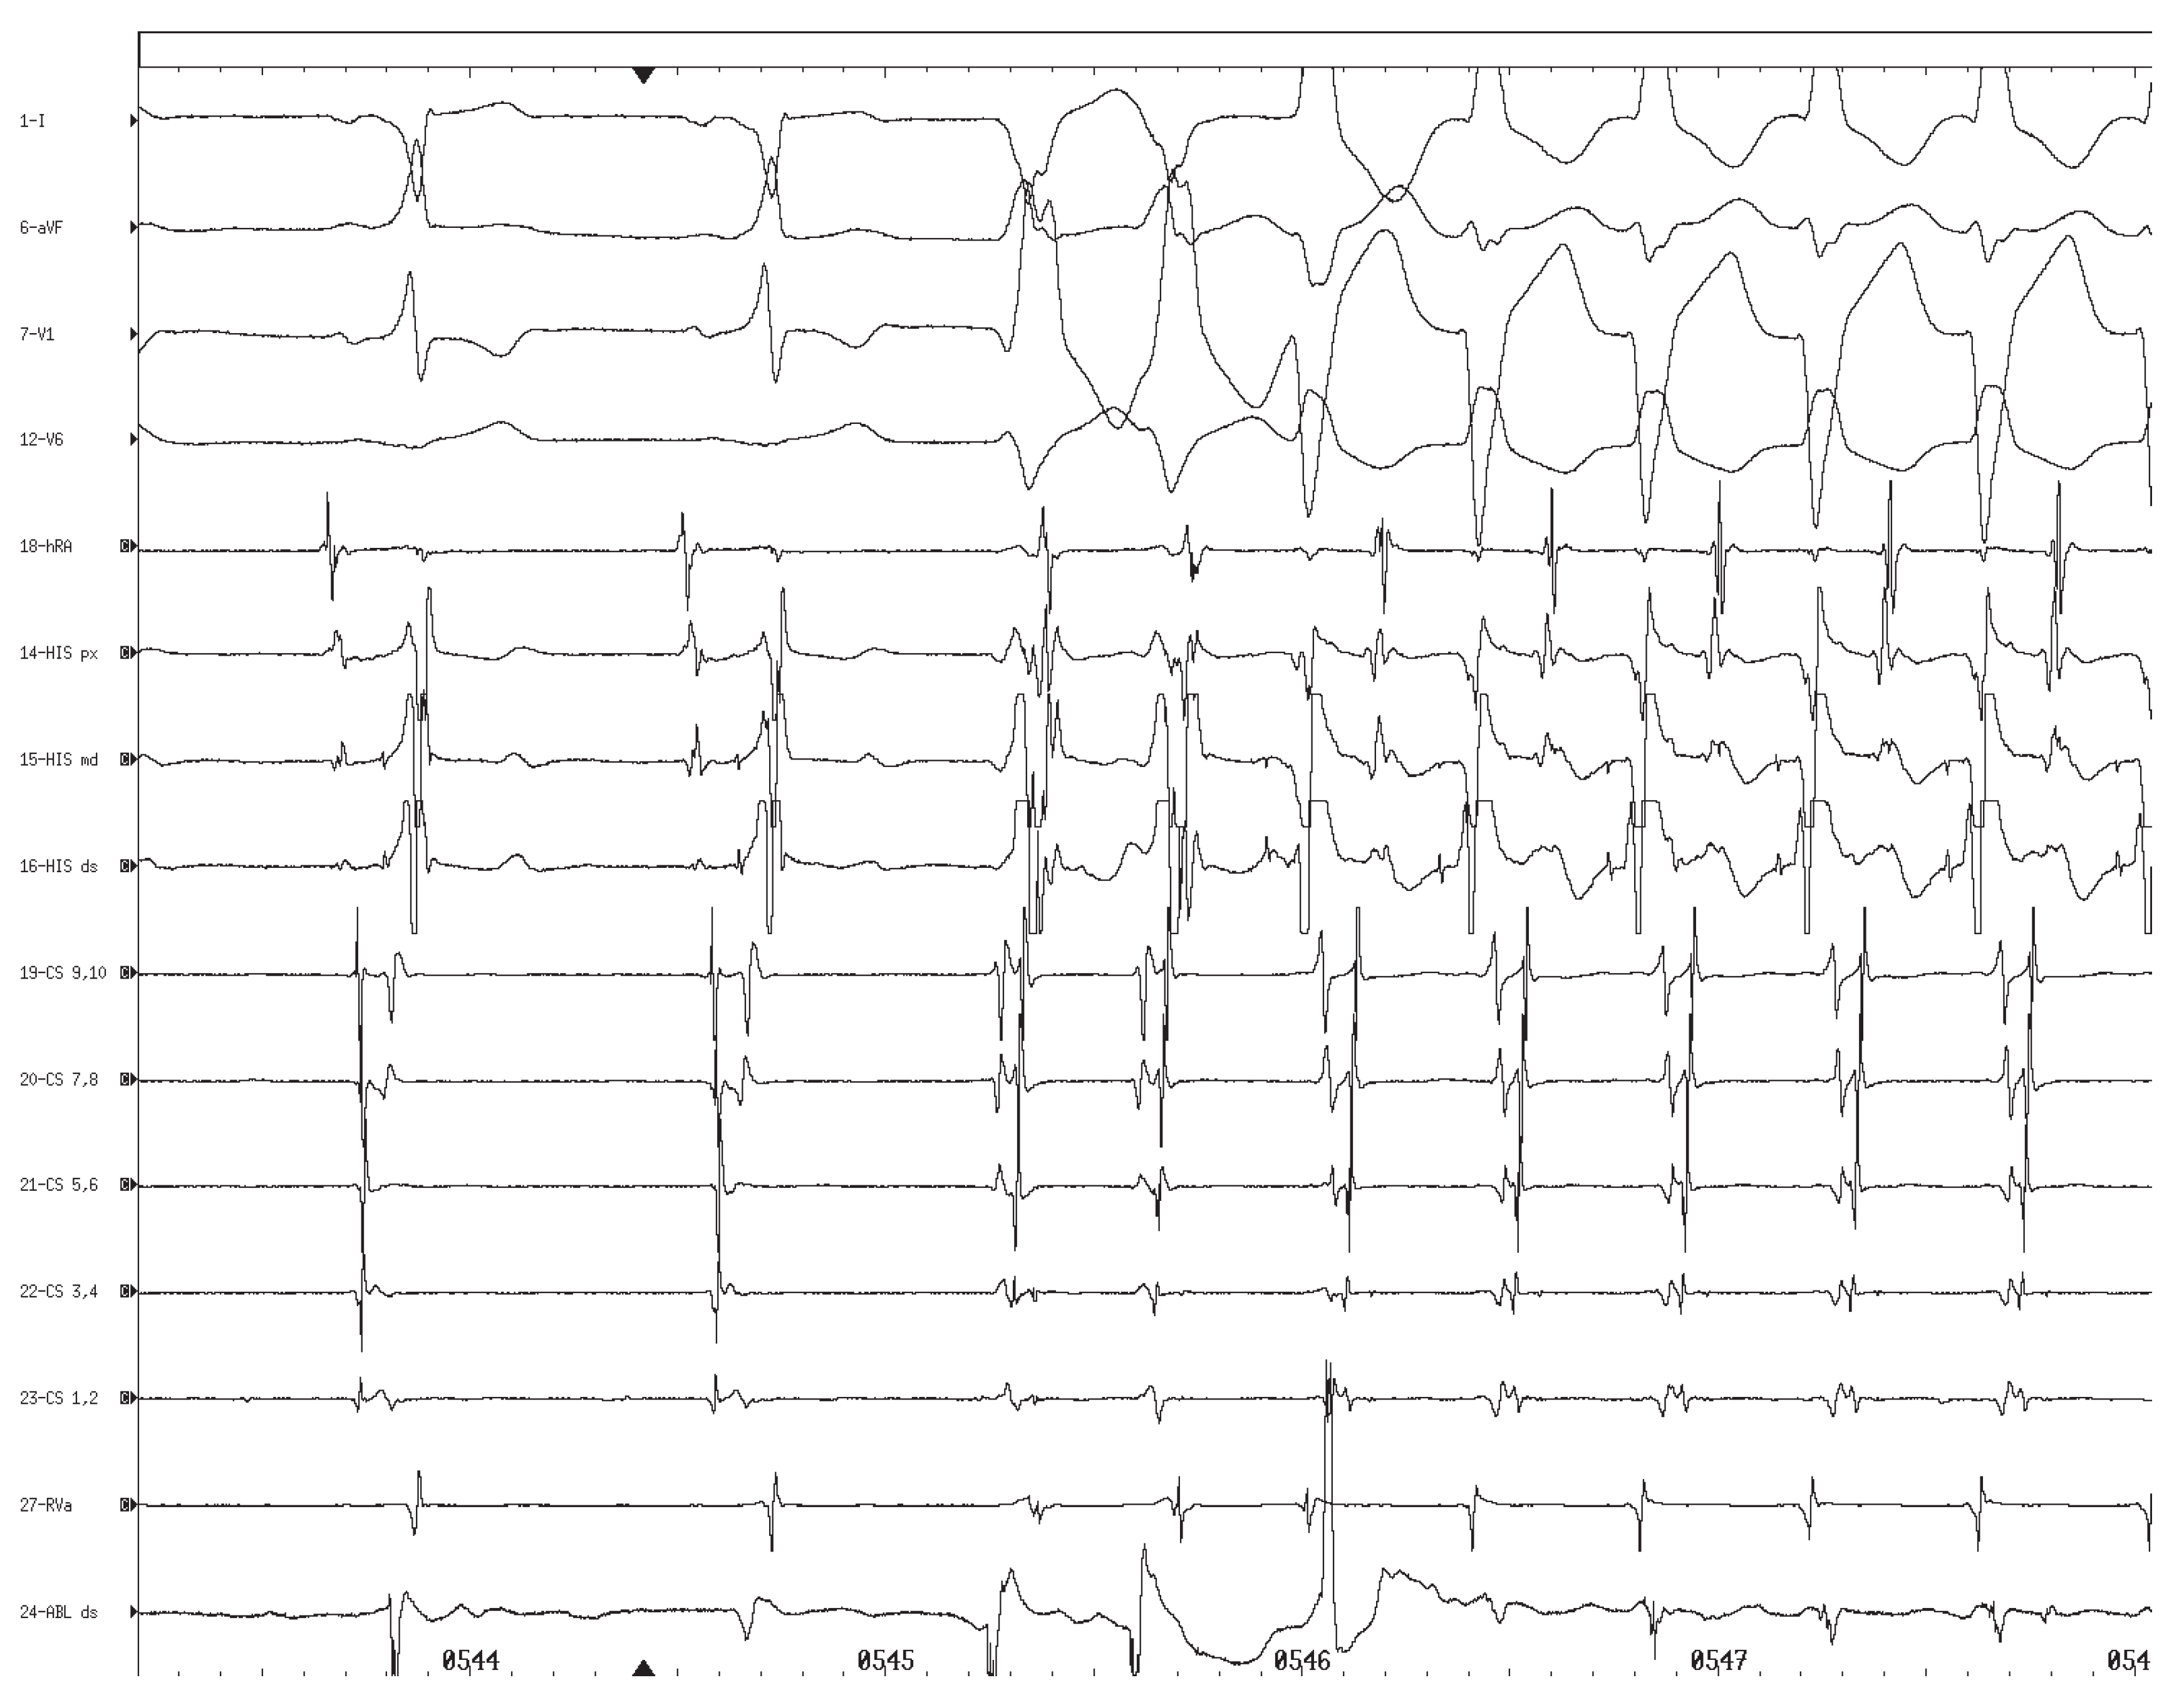

A 15-year-old male with a 3-month history of recurrent tachycardias was referred to our hospital for further evaluation. Although most of the tachycardias were regular, certain episodes were described as irregular. The electrocardiogram (ECG) showed a preexcitation pattern compatible with the presence of Wolff-Parkinson-White syndrome with a left free wall accessory pathway (fig. 1A). During an electrophysiologic study atrial fibrillation with a fast ventricular rate (minimum cycle length 186 ms) was induced. Subsequently, ventricular rate was reduced by intravenous administration of propafenone (70 mg) and sinus rhythm was restored by cardioversion (200 Joule) under sedation with midazolam (4 mg i.v.). During transaortic insertion of a 7 F, 4 mm tip ablation catheter (Marinr, Medtronic Inc., Minneapolis, MN, USA) orthodromic circus movement tachycardia with a LBBB pattern was induced (fig. 2). Shortly after spontaneous termination of this arrhythmia a change of the QRS morphology suggesting full preexcitation due to blockade of antegrade conduction via the AV node was noted (fig. 3). Because of the imminent risk of recurrent episodes of atrial fibrillation with fast ventricular rates we decided to proceed to RF catheter ablation of the accessory pathway after prophylactic insertion of a right ventricular pacing catheter. Within seconds after the onset of RF energy delivery, complete AV-block with alternating junctional escape rhythm with LBBB aberration and idioventricular rhythm of RBBB pattern was noted (fig. 4). RF energy was discontinued immediately which was followed by restoration of accessory pathway conduction resulting in sinus rhythm with full preexcitation suggesting compromised nodal AV conduction. The second RF burn was, again, followed by complete AV-block with junctional escape rhythm of LBBB pattern. However, after 20 seconds AV conduction via the AV node recovered with residual first degree AV-block and LBBB. Because of recovery of accessory pathway conduction a third RF burn was delivered, leading to sustained interruption of accessory pathway conduction associated with normal AV node conduction and LBBB. After catheter removal, the patient was observed in the cardiac care unit for 12 hours. During this time the LBBB resolved with restoration of normal infranodal conduction and without recurrence of accessory pathway conduction. At a 3-month follow-up visit the patient had remained asymptomatic and the ECG was normal (fig. 1B).

Figure 4. Complete atrioventricular block with alternating junctional escape rhythm with left bundle branch block aberration and idioventricular rhythm of right bundle branch block pattern. Note the presence of a His potential in the first two complexes indicating the presence of atrioventricular block at the nodal level in combination with left bundle branch block. Ventricular cycle length 1500 ms.